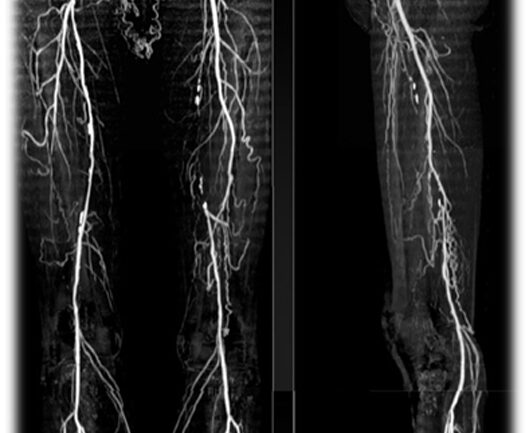

Angiografía

Un material de contraste es inyectado en los vasos sanguíneos, esta prueba le permite al médico ver el flujo sanguíneo en las arterias en tiempo real. El médico puede rastrear el flujo del material de contraste mediante técnicas de diagnóstico por imágenes, como radiografías o procedimientos llamados angiografía por resonancia magnética (ARM) o angiografía por tomografía computarizada (ATC).

La angiografía con catéter es un procedimiento más invasivo que consta de guiar un catéter a través de una arteria en la ingle hacia el área afectada e inyectar el tinte de esa manera. Aunque es invasivo, este tipo de angiografía ofrece un diagnóstico y un tratamiento simultáneos. 3

4.Florida Cardiology,P.A. Angiografía de Extremidades (superior e Inferior.[monografía en Internet].2016.[acceso 30 de enero 2020]. Disponible en https://flcard.com/es/extremity-angiography-upper-and-lower/